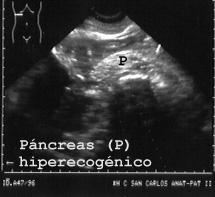

21PANCRE.JPG (17132 bytes)

Fig 21

En esta imagen también se observa el estómago encima del páncreas. El páncreas en el cadáver suele tener un aspecto más hiperecóico (blanco), que en vida y se aprecia en esta figura.